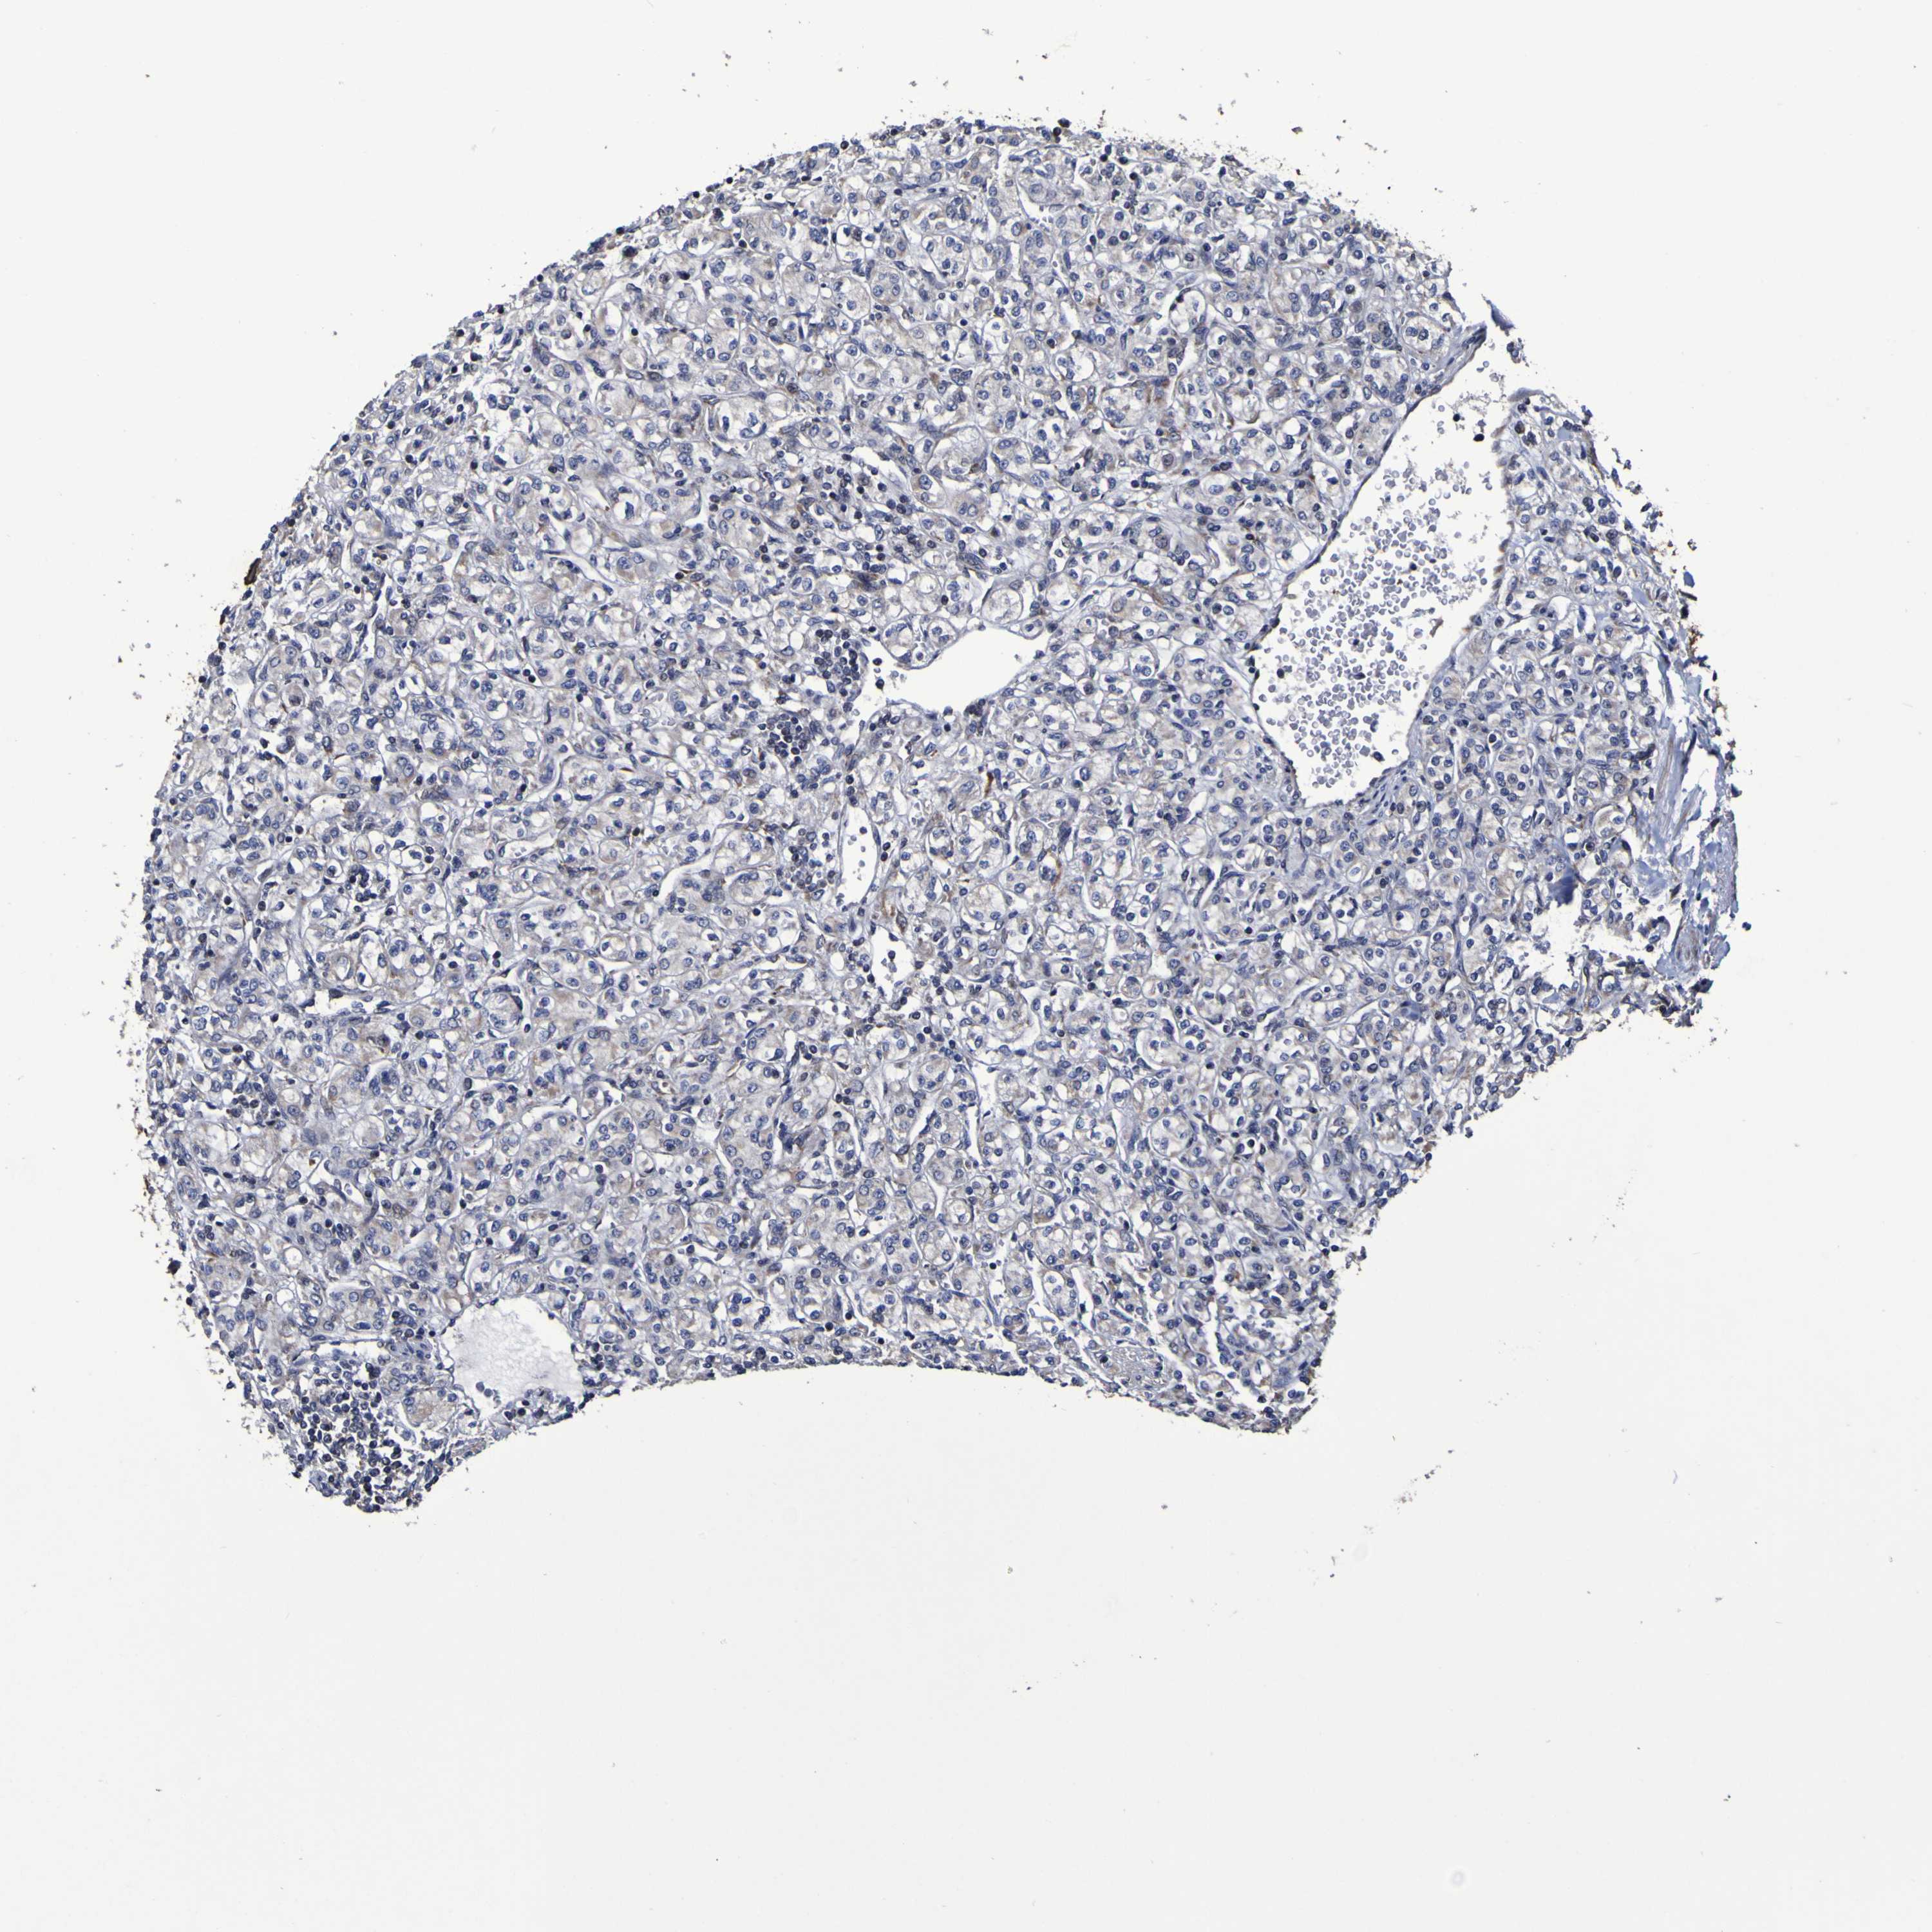

KIDNEY CHROMOPHOBE (TCGA) - Interactive survival scatter ploti

The Survival Scatter plot shows the clinical status (i.e. dead or alive) for all individuals in the patient cohort, based on the same data that underlies the corresponding Kaplan-Meier plots. Patients that are alive at last time for follow-up are shown in blue and patients who have died during the study are shown in red.

The x-axis shows the expression levels (FPKM) of the investigated gene in the tumor tissue at the time of diagnosis. The y-axis shows the follow-up time after diagnosis (years). Both axes are complimented with kernel density curves demonstrating the data density over the axes. The top density plot shows the expression levels (FPKM) distribution among dead (red) and alive patients (blue). The right density plot shows the data density of the survived years of dead patients with high and low expression levels respectively, stratified using the cutoff indicated by the vertical dashed line through the Survival Scatter plot. This cutoff is automatically defined based on the FPKM cutoff that minimizes the p-score. The cutoff can be changed by dragging the vertical line or by entering a cutoff value in the square labeled "Current cut-off".

Under the Survival Scatter plot the p-score landscape (black curve; left axis) is shown together with dead median separation (red curve; right axis). Dead median separation is the difference in median mRNA expression between patients who have died with high and low expression, respectively. It is calculated as follows: median FPKM expression of dead patients with high expression - median FPKM expression of dead patients with low expression. This is intended to aid the user in visually exploring custom cutoffs and the associated p-scores and dead median separation.

Individual patient data is displayed and can be filtered by clicking on one or more of the category buttons on the top of the page. Categories describing expression level and patient information include: high, low, alive, dead, female, male and tumor stages. The scale of the x-axis can be toggled between linear and log-scale by clicking on the "x log" button. Mouse-over function shows TCGA ID, patient information and mRNA expression (FPKM) for each patient.

& Survival analysisi

Kaplan-Meier plots summarize results from analysis of correlation between mRNA expression level and patient survival. Patients were divided based on level of expression into one of the two groups "low" (under cut off) or "high" (over cut off). X-axis shows time for survival (years) and y-axis shows the probability of survival, where 1.0 corresponds to 100 percent.

P3H1 is not prognostic in Kidney Chromophobe (TCGA)

Best expression cut offi

: 4

P scorei

N/A

TCGA RNA samplesi

Average pTPM 7.0

Number of samples 64